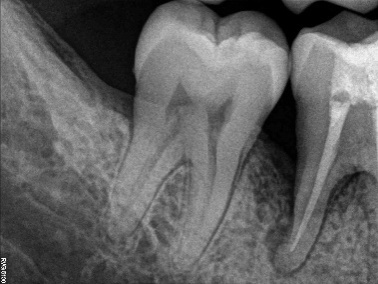

An apparently healthy 27-year-old male patient reported to the Department of Periodontics, College of Dental Sciences, Davngere, Karnataka, with a chief complaint of food lodgment in the lower right back tooth region since two years. Periodontal findings revealed periodontal pocket distal to the mandibular right first molar and the tooth was vital. Intraoral periapical radiograph (IOPA) showed a vertical bony defect distal to mandibular right first molar up to the apical third, with periodontal space widening in the furcation. Based on this history, clinical findings and radiographic evaluation, a diagnosis of localized periodontitis was reached.

Figure 4. Baseline radiovisiograph (RVG) of the right mandibular first molar region; vertical bony defect distal to the mandibular right first molar up to the apical third and periodontal space widening in the furcation area.